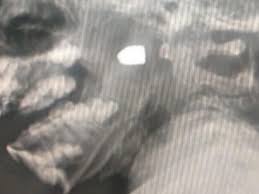

Allison, la menor, fue llevada a un hospital cercano, le tomaron radiografías y comprobaron que el proyectil se había alojado en su garganta; ahora se debate entre la vida y la muerte.